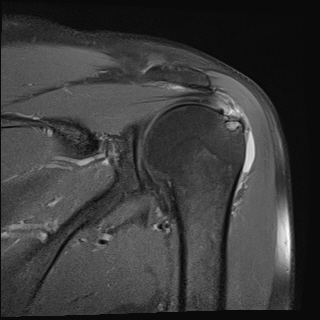

ŽÃËÀÚ¸¦ °ßºÀ ¿ÜÃø¿¡ ´ë°í ÆÈÀ» ¿ÜÀüÇϸ鼭 ´ë°áÀý°ú °ßºÀÀÇ Ãæµ¹À» °üÂûÇÏ´Ï °ßºÀ¿ÜÃø¿¡

¼ö¾×ÀÌ Àú·ùµÇ¾î ¿ÜÃø Ãæµ¹ÁõÈıºÀÌ È®ÀεǾú´Ù(÷ºÎ ÆÄÀÏ 1).